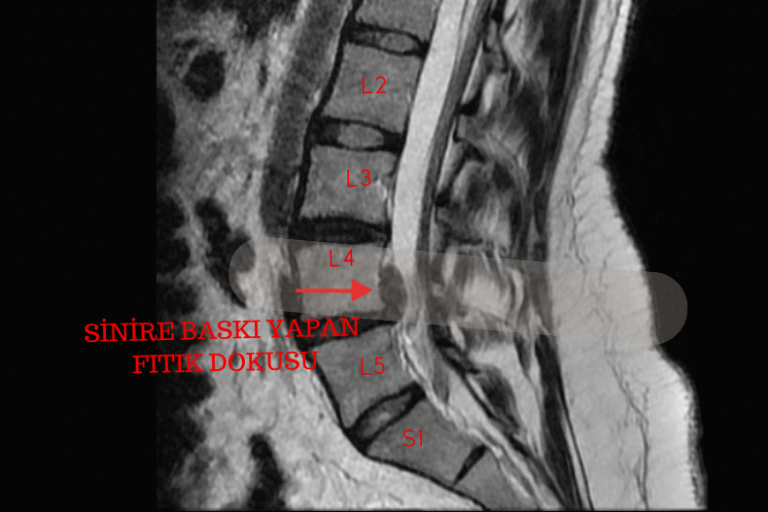

L4-5 fıtık ameliyatı nedir, belirtileri nelerdir? Ne zaman ameliyat gerekir, riskleri ve iyileşme süreci hakkında bilmeniz gerekenler burada.

Bel fıtığı belirtileri, nedenleri ve tedavi yöntemleri hakkında bilmeniz gerekenler.